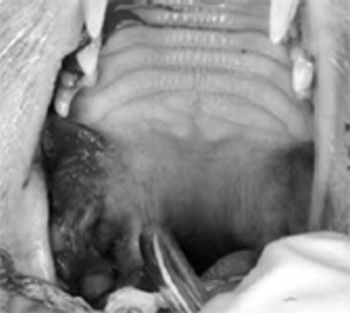

A good clinical oral examination is one of the most important tools we have for diagnosing many dental and oral problems. However, much of the pathology in the oral cavity involves the roots and supportive bone of the teeth instead of their visible crowns.

Familiarity with the normal structures and physiology of the oral cavity is a powerful tool to help identify what is not normal. Detailed examination of many normal mouths is the best way to acquire expertise.

The many abnormalities, lesions and diseases that are commonly found in the oral cavity become much easier to recognize after one has become familiar with the normal oral anatomy and structures. The most common and most obvious problems, such as periodontal disease and fractured teeth, are easy to identify during routine oral examinations.